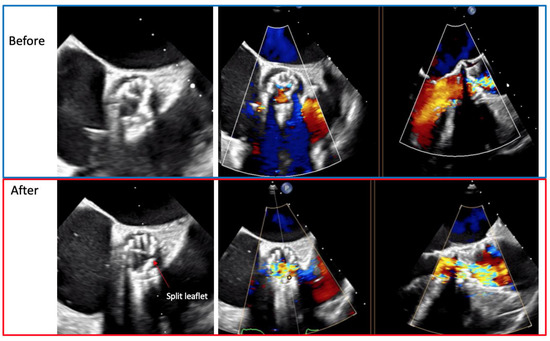

6.3. Procedure